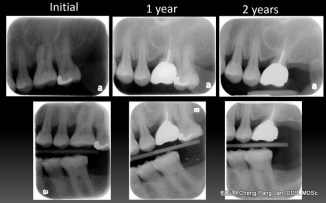

拔牙或植牙?

老師常常暗示著大家,implant與natural teeth之間,留下natural teeth比較好。這個我真的相信,在牙周病科的每一位學弟妹也都相信,甚至我相信週六在場的牙周病醫師都認同,但是大家有沒有想過,每隔週三一起開會的Prosthodontist、 Orthodontist都相信嗎?甚至,從實習醫師畢業就進入職場服務病人的學弟妹們,都相信嗎?

問題不在Implant or Natural teeth二選一,問題在於大家都想學implant,而我們應該教所有醫師正確的implant treatment planning ,或分享正確的implant treatment philosophy,這樣才可以服務更多的病人,更多的病人可以得到更好的效果。implant therapy是未知的,所以大家會擔心,但是光是擔心是不夠的,我覺得要了解後再擔心,這些包含多看文獻、多聽演講,不過真正我認為最重要的,還是要學會獨立思考─分辨什麼是對的、什麼是錯的,全由自己判斷,不受他人影響。台大的環境與許多老師,真正教我的是學習如何獨立思考,這是最大的收穫。